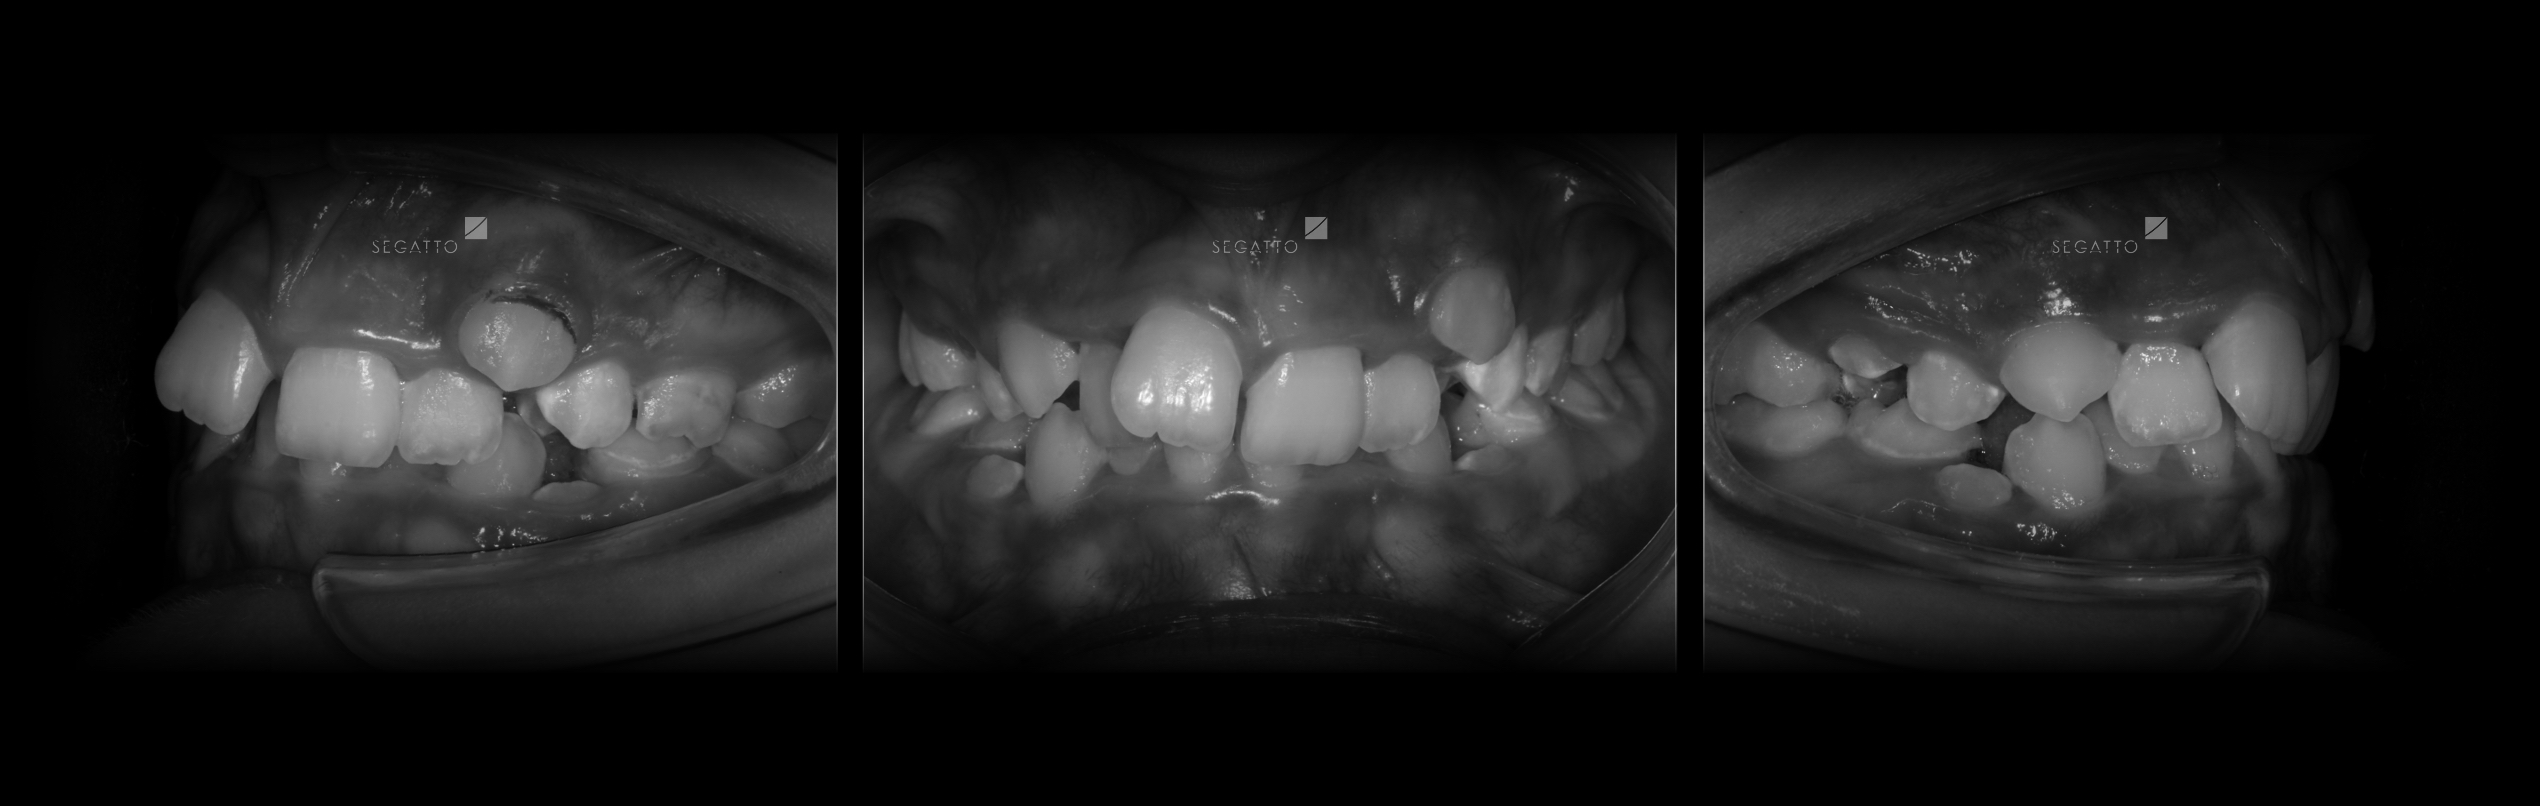

Orthodontics

Cases